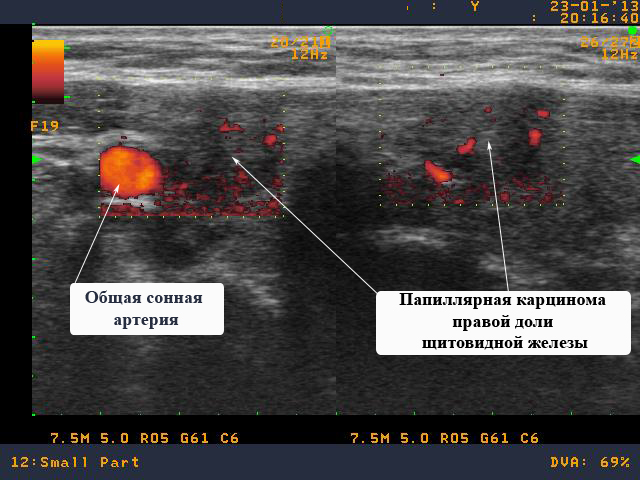

Папиллярный рак правой доли щитовидной железы

В данном клиническом случае представлена пациента К. 43 лет из города Луга (Ленинградская область). Пациентка обратилась на очную консультацию, во время которой, было выполнено УЗИ щитовидной железы и обнаружен узел в правой доле щитовидной железы размерами 15 на 13 на 19 мм.